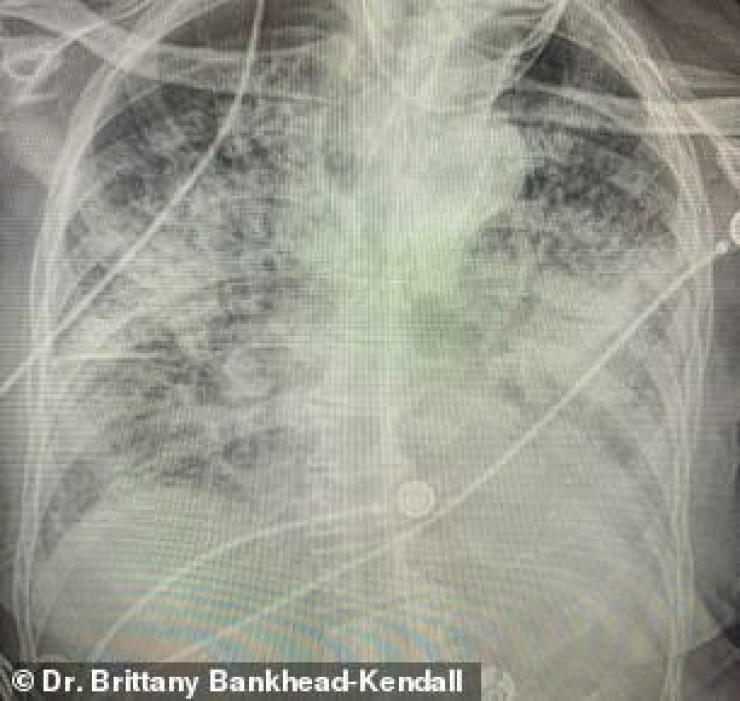

По словам хирурга, легкие выздоровевших пациентов с COVID-19 выглядят намного хуже, чем у курильщиков. Снимок выглядел почти полностью белым. Врач пояснила, что помутнение легких обычно указывает на то, что они наполнены такими веществами, как жидкость или бактерии, а также плотными рубцами и повреждениями.

"Легкие после коронавируса выглядят хуже, чем любые ужасные легкие курильщика, которые мы когда-либо видели. И они разрушаются", - заявила она.

По ее словам, многие эксперты в области здравоохранения концентрируют внимание на показателях смертности, а не на долгосрочных последствиях выживших. Доктор Бэнкхед-Кендалл также отметила, что почти у всех пациентов из тех, кого она лечила, и тех, кто переболел коронавирусом, был плохой рентген грудной клетки.